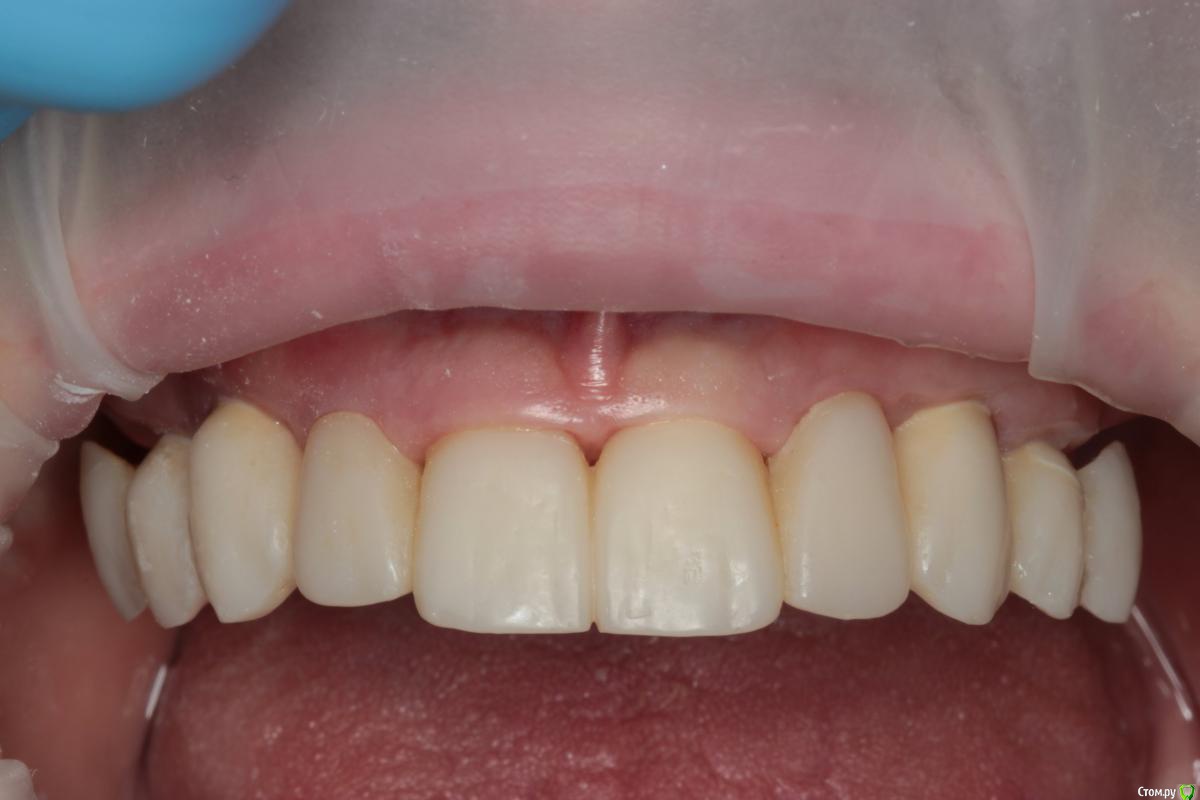

Популярный пост Abuk Опубликовано 24 ноября, 2015 Популярный пост Поделиться Опубликовано 24 ноября, 2015 Планировали 8 имплантатов.Буду рад конструктивной критике.Фото с мокап.Через 6 днейДалее хотели поставить 6 ки, она отказалась (не хотели синусы)и решили все по-другому .Через 2мес пришла с отколотыми консолями )Прошу прощения ,что ортопедию выложил не в том разделе), не хотел делить. 26 1 Ссылка на комментарий

Abuk Опубликовано 24 ноября, 2015 Автор Поделиться Опубликовано 24 ноября, 2015 (изменено) Радикально Вы. Что оставили ей после имплантации-это инд аббатменты? На них мокап одели и нагрузили сразу? У всех был торк хороший? Или это временные абб? Что за систему использовали? В планах консоль назад, правильно я понимаю?Спасибо.увидев такую работу,сам так же подумал бы). Но там подвижность 2-3 ст. ближе к 3. Мосты болтались ,2 ки в хлам. 1 ки только стабильны. Снимал мосты,проводил кюретаж. Решил дернуть.Абатманы временные, тех. сделал на них коронки. Система анкилоз. Работа,на посл. фото, постоянная . Имплы в области 4 и по одному моляру ,консоли. Мок ап был до имплантации . По нему шаблон. Стабильность 15 -20 на 23 , остальное больше 30. Изменено 24 ноября, 2015 пользователем Abuk 1 Ссылка на комментарий

Abuk Опубликовано 24 ноября, 2015 Автор Поделиться Опубликовано 24 ноября, 2015 Вы лунки тоже аугментиовали?Хирургия понравиласьДа, спасибо. Если не сложно, напишите что вам не понравилось в ортопедии.Техничка мне самому не очень , хотя многим ,включая пациента, понравилась Ссылка на комментарий